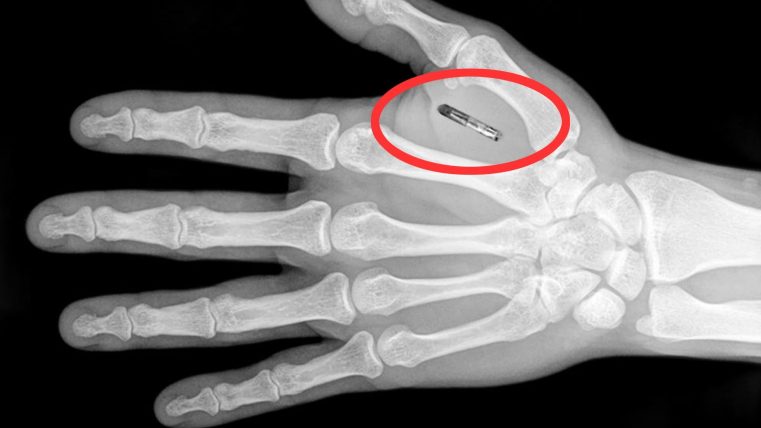

În Suedia, un pionier în ceea ce se numește „biohacking (tehnica prin care sunt adăugate dispozitive cibernetice la corpuri vii)”, estimează că până la 4.000 de microcipuri au fost implantate, de obicei pentru „confort”, transformând mâinile oamenilor care le-au acceptat în carduri de credit, cartele de acces în diverse locuri și chiar bilete de călătorie. Microcipurile sunt injectate în partea din spate a mâinii între degetul mare și degetul arătător.